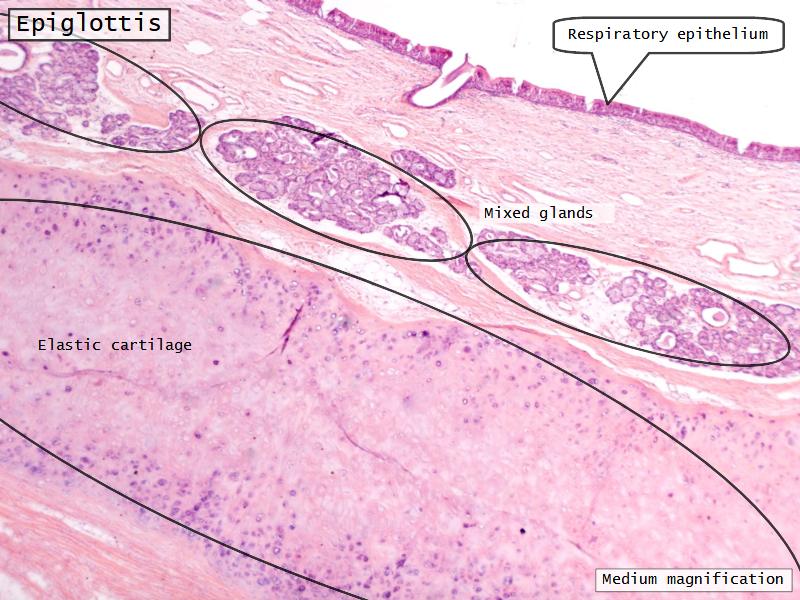

- Slide 111: Epiglottis

Epiglottis

Respiratory epithelium

- Pseudostratified

- Ciliated

- Columnar

- Epithelium with

- 4 Cells

- Ciliated columnar cells

- Non-ciliated columnar cells

- Goblet cells

- Basal cells